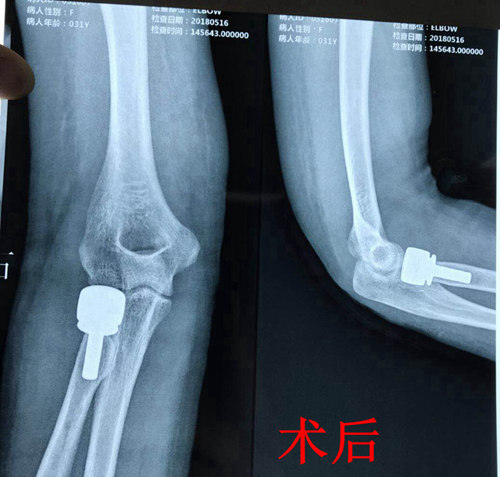

『市内首例』骨一科成功完成一例右桡骨小头粉碎骨折人工桡骨小头置换术

近日,我院骨一科成功完成一例右桡骨小头粉碎骨折人工桡骨小头置换术,该项技术的成功开展填补了我院乃至全市人工桡骨小头置换术的空白。

患者,青年女性,摔伤致右肘部疼痛伴活动受限1月余入院。入院后行拍片、CT检查示:右桡骨小头粉碎骨折。

考虑到患者系粉碎骨折,科室立即组织会诊讨论,最终决定由副院长杜敏指导,科室副主任张延平主刀,主治医师王陇协助行人工桡骨小头置换术,手术过程顺利,无并发症发生,术后患者病情平稳。目前患者前臂已行旋转功能锻炼,恢复良好。